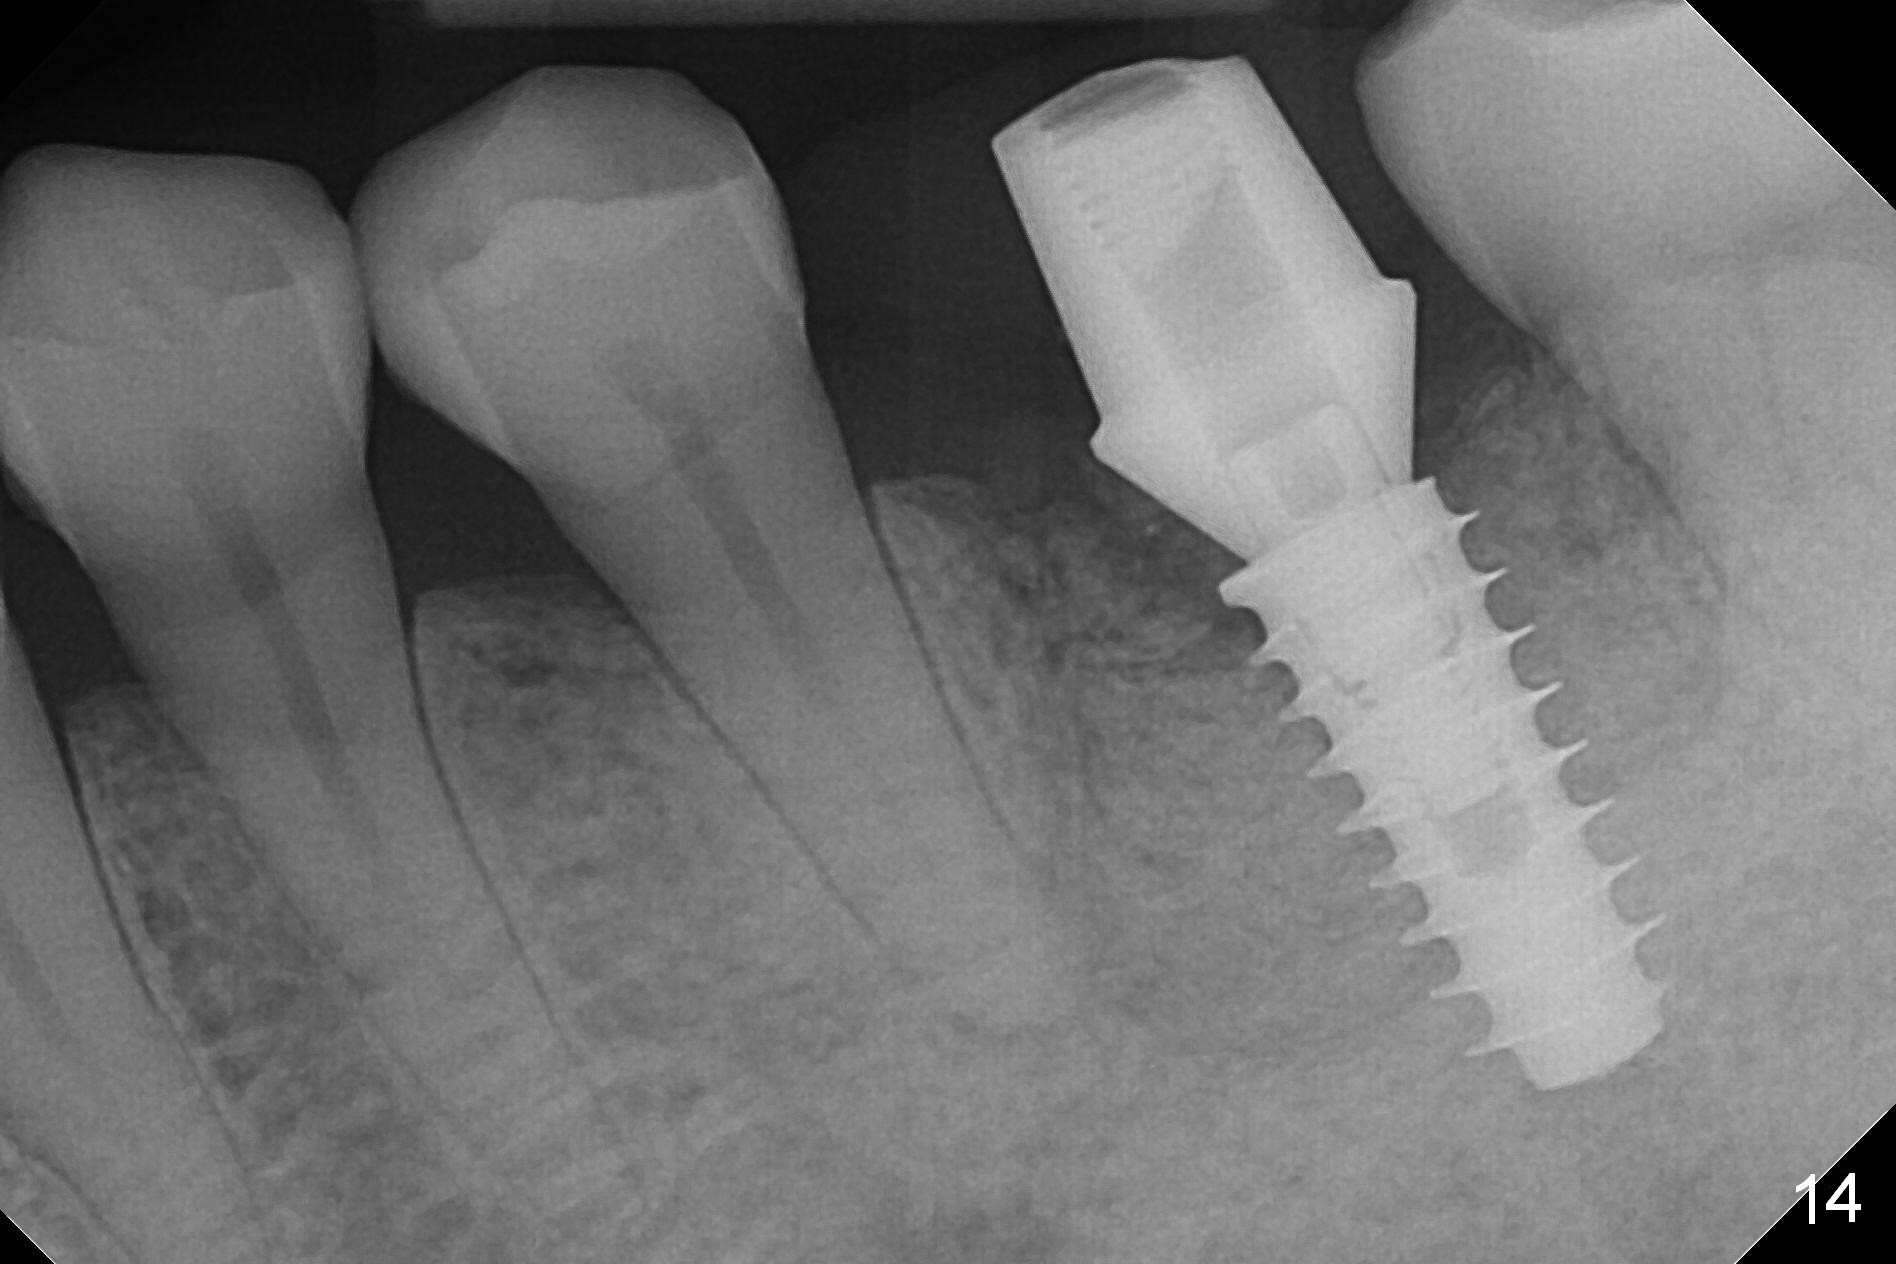

There is a new pattern of bony trabeculae around the implant 4.5 months postop (Fig.14). Bone density increases 1 year 4 months post cementation (Fig.15).